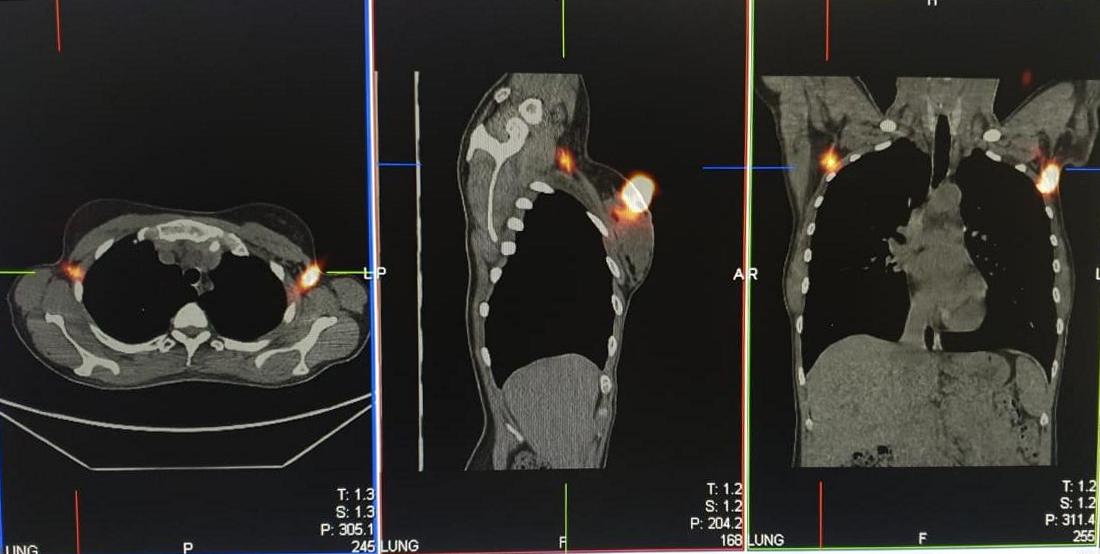

Применяемый при сцинтиграфии сигнальных лимфоузлов радиофармпрепарат «99mTc-Технефит» используется также для сцинтиграфии печени и селезенки, а также лимфосцинтиграфии верхних и нижних конечностей. Это коллоидный препарат, в котором в качестве метки используется радиоактивный изотоп Технеция-99m. В состав радиофармпрепарата входят коллоидные частицы очень маленького диаметра, это позволяет использовать его для сцинтиграфии сигнальных лимфатических узлов. Выполняется внутрикожное, подкожное или перитуморальное (в паренхиму пораженной молочной железы) введение, после чего меченные изотопом коллоидные частички по лимфатическим сосудам проникают в лимфатические узлы и там оседают. Первый лимфатический узел, накапливающий радиофармпрепарат на пути лимфатического оттока от опухоли молочной железы, и является сигнальным или сторожевым.

Данные сцинтиграфии и ОФЭКТ (однофотонной эмиссионной компьютерной томографии) сторожевых лимфатических узлов |

«Сторожевой лимфоузел, который самым первым захватывает меченные радиоизотопом коллоидные частицы на пути лимфооттока от опухоли молочной железы, также первым встречает метастатические опухолевые клетки. Этот лимфатический узел удаляют при интраоперационной биопсии сигнальных лимфоузлов. А далее, пока идет операция, удаленный материал отправляют на исследование с предварительным измерением его радиоактивности (она, как правило, ниже минимально значимого уровня, что позволяет передать его в патологоанатомическое отделение)», — комментирует заведующий отделением радиологии Центра Алмазова к.м.н. Ольга Васильевна Юдина.